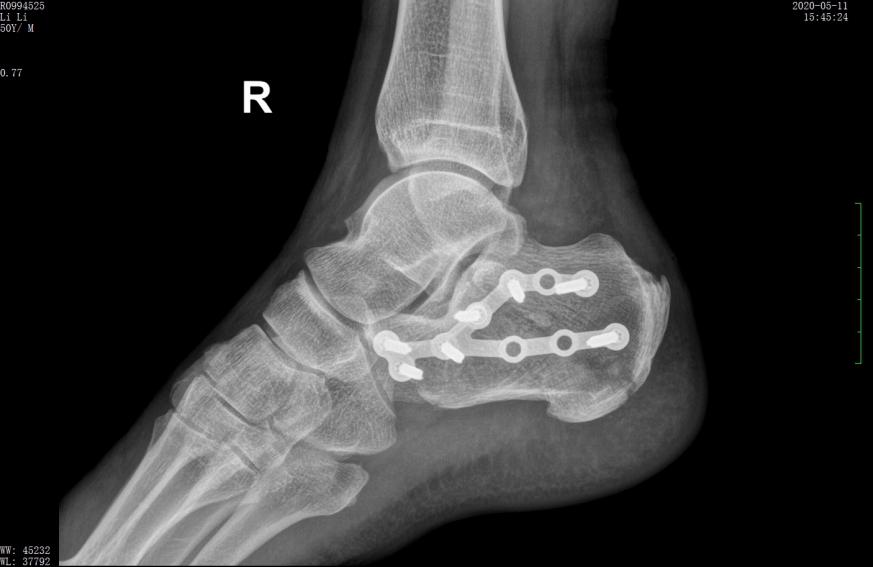

L形外侧切口 | 术后

行微创手术治疗后,跟骨高度恢复,关节面平整

术后X线示骨折复位良好